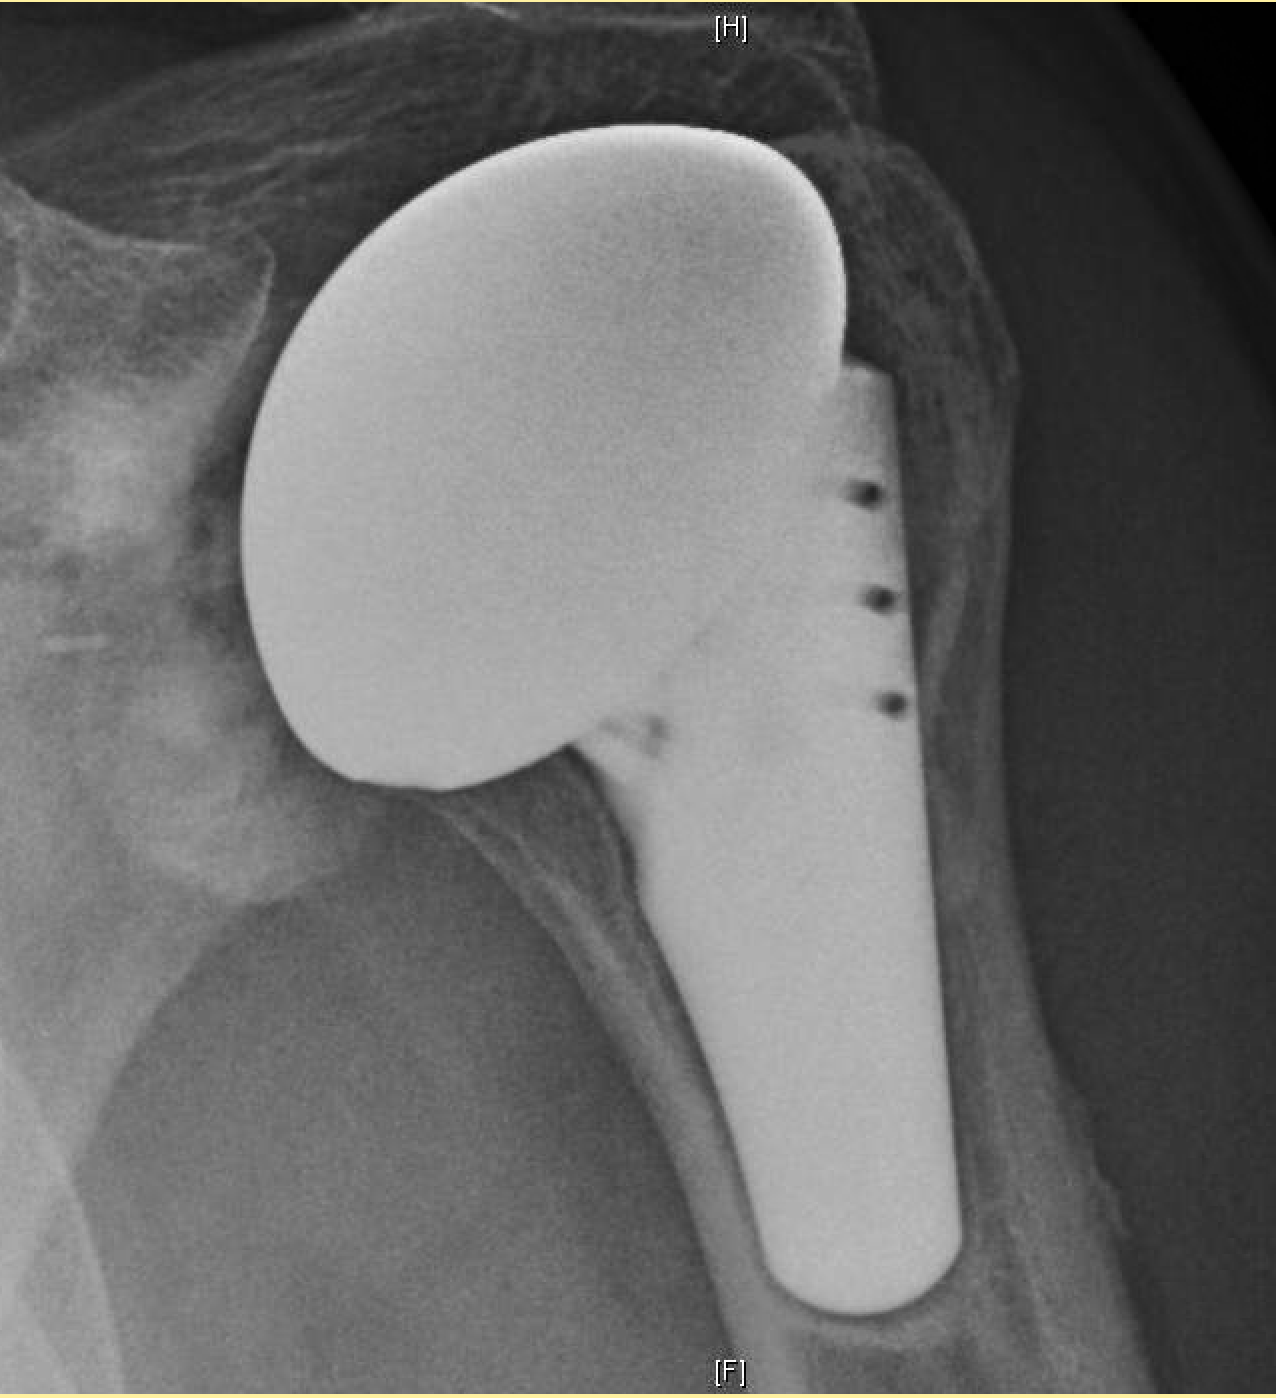

Shoulder Arthritis / Rotator Cuff Tears / Shoulder Pain Rotator Cuff Surgery Infection the outcomes after arthroscopic rotator cuff repair (rcr) have been reported to be successful. However, more than 50% of patients may require. deep infection after rcr can be treated with open or arthroscopic debridement. The incidence of deep infections (defined as an. the role of c acnes causing postoperative infection following shoulder surgery is being increasingly recognized.. Rotator Cuff Surgery Infection.

Shoulder Arthritis / Rotator Cuff Tears / Shoulder Pain Total Rotator Cuff Surgery Infection The incidence of deep infections (defined as an. the role of c acnes causing postoperative infection following shoulder surgery is being increasingly recognized. However, more than 50% of patients may require. the incidence of infection after rotator cuff repair and shoulder arthroplasty ranges from 0.27 to 1.9 % and. deep infection after rcr can be treated with. Rotator Cuff Surgery Infection.

Shoulder Arthritis/Joint Replacement Rotator cuff tears Single stage Rotator Cuff Surgery Infection the incidence of infection after rotator cuff repair and shoulder arthroplasty ranges from 0.27 to 1.9 % and. The incidence of deep infections (defined as an. However, more than 50% of patients may require. the outcomes after arthroscopic rotator cuff repair (rcr) have been reported to be successful. propionibacterium acnes has been implicated as a cause of. Rotator Cuff Surgery Infection.